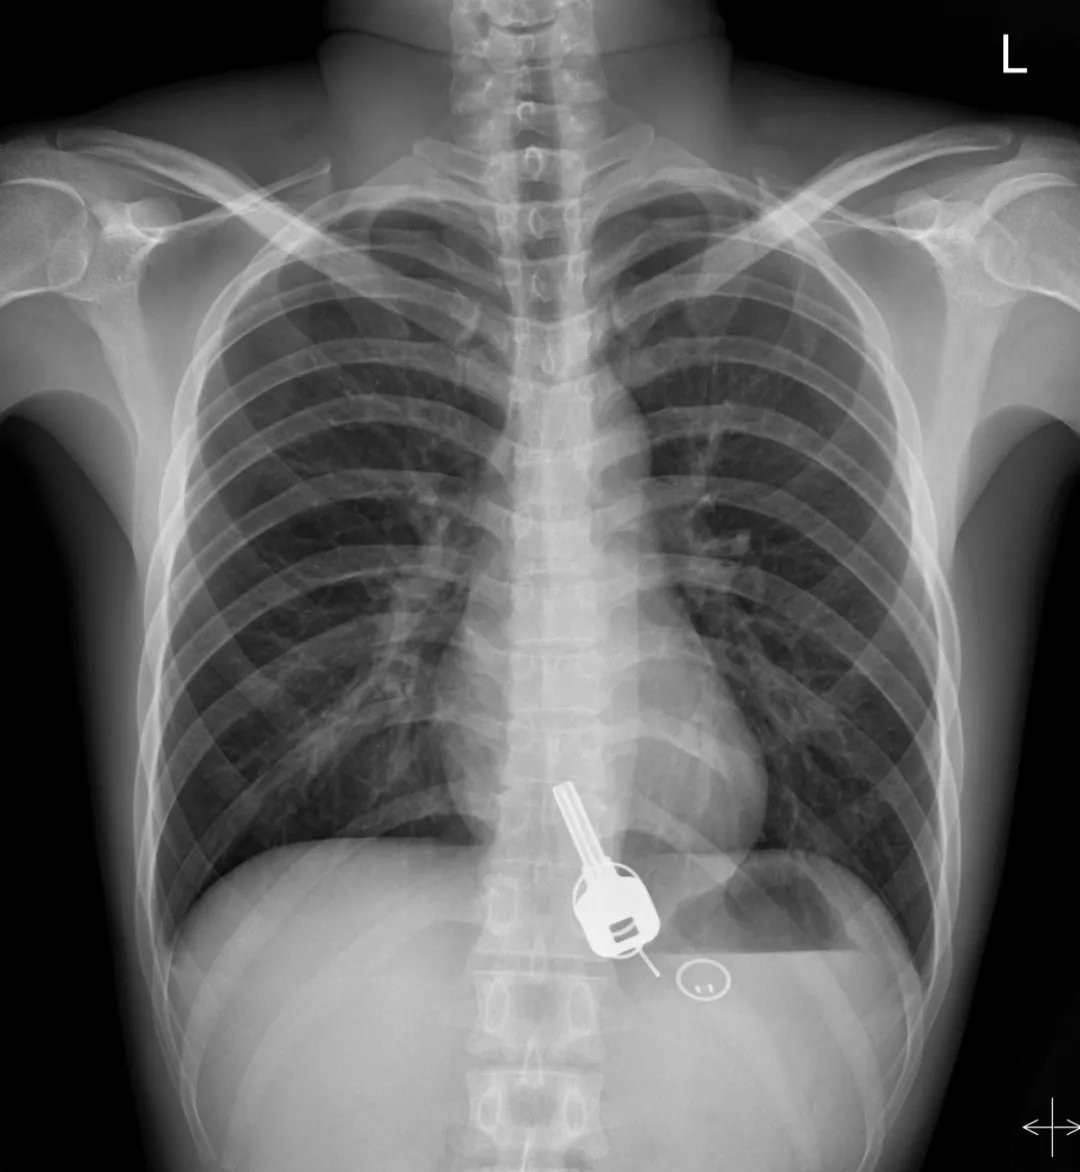

廣東東莞的常先生酒后回家找不到鑰匙,酒醒后他感到胸口疼痛,去醫(yī)院一查,發(fā)現(xiàn)一把鐵鑰匙、2個(gè)鑰匙扣、1個(gè)門禁牌清楚顯示在肚子胃區(qū)的位置上。

醫(yī)生準(zhǔn)備在胃鏡下取出鑰匙,不料,因鑰匙太大在常先生喉嚨附近食管入口處卡住了,取不出來,最后,醫(yī)生決定給常先生做無痛胃鏡,麻醉后,常先生食管入口處肌肉松弛,鑰匙終于順利取出!。